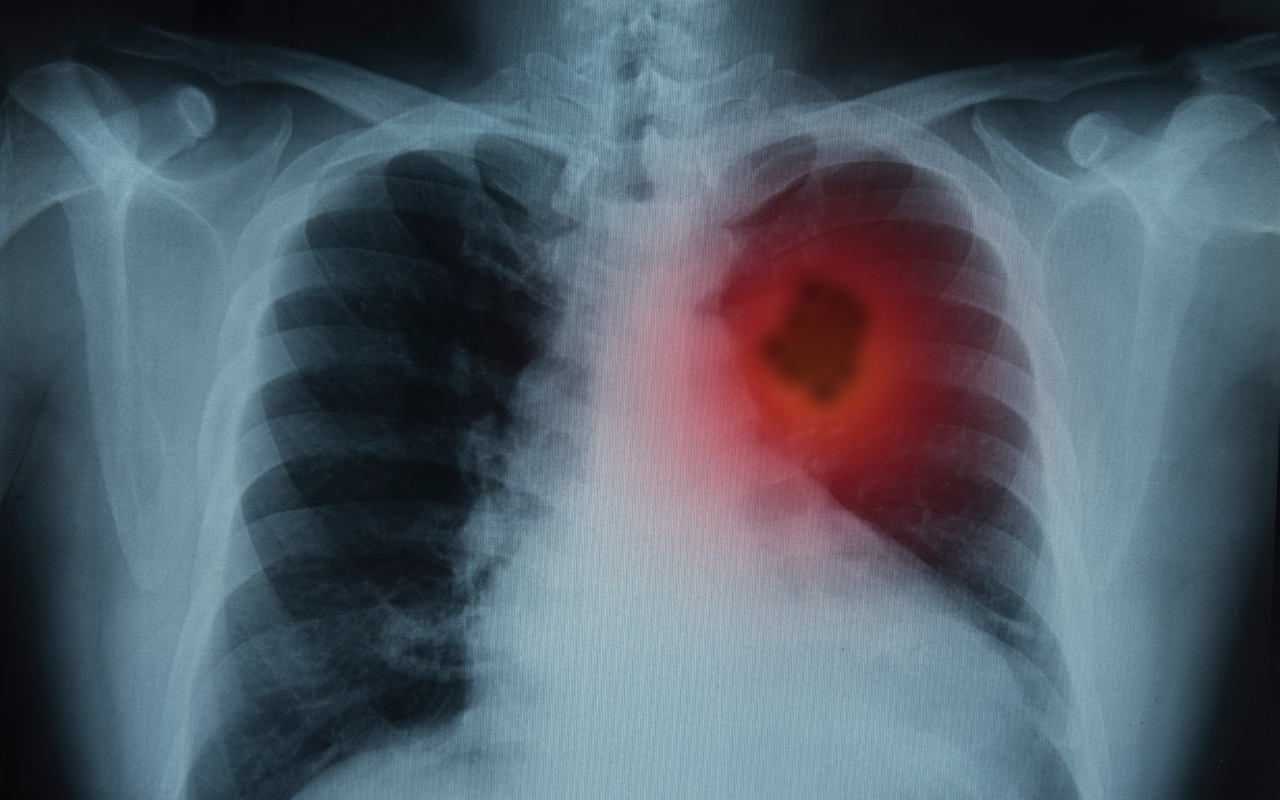

The program will refer individuals aged 50–70 years with a significant history of cigarette smoking for an low dose computed tomography (LDCT) to help identify lung cancer at an early stage where survival rates are substantially improved.

Aboriginal and Torres Strait Islander peoples have a disproportionate burden of lung cancer in Australia, experiencing double the rates of lung cancer compared with non-Indigenous populations.